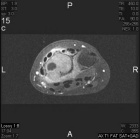

18 year old female with persistent and worsening wrist pain for four months